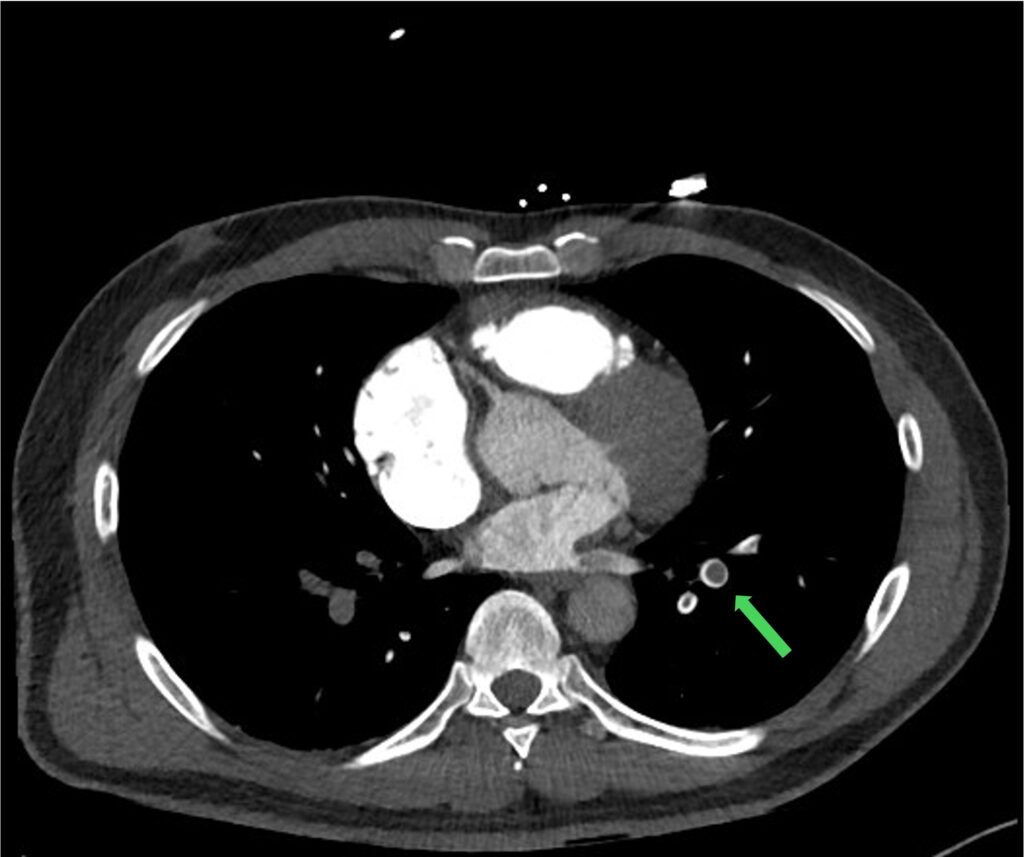

Figure 1: CT chest without contrast

Figure 2: CTPA with contrast within the bifurcation of the main PA